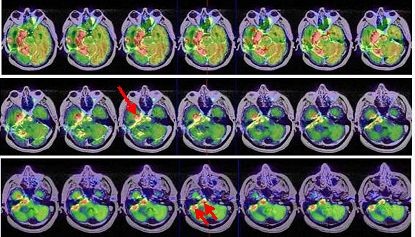

La terapéutica tras el estudio PET-RNM cerebral consistió en radiocirugía, utilizando la Guía de Estereotaxia Brainlab, imágenes de fusión RNM-CT para planificación, fotones de 6 MV con técnica de arcoterapia dinámica conformada con un microcolimador multilámina Brainlab, administrando una dosis máxima de 22 Gy en la lesión temporal derecha, una dosis de 20 Gy al margen de la lesión, 0,8 Gy en las vías ópticas, 7 Gy en troncoencéfalo y 1,4 Gy en quiasma. La RNM cerebral de control mostró cambios postratamiento en la zona más caudal del lóbulo temporal derecho. Al cabo de 3 años, el paciente refiere cefalea aguda, discreta bradipsiquia y alteración de la marcha por hemiparesia izquierda. La RNM informa persistencia tumoral en región mesial posterior temporal derecha con infiltración en región más posterior del lóbulo temporal que afecta y atraviesa el tentorio, con compromiso del lóbulo cerebeloso derecho. Un estudio PET-RNM cerebral confirma la recurrencia tumoral (fig. 2).